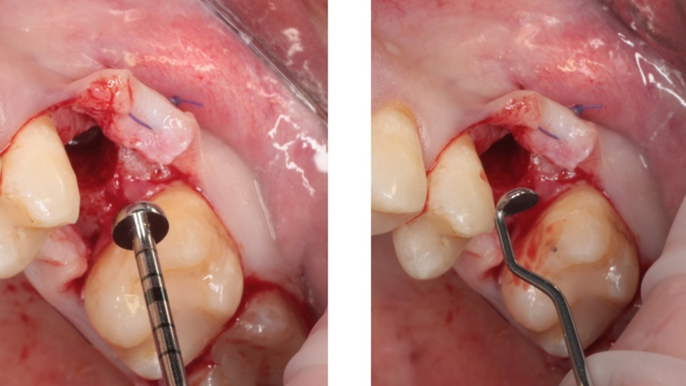

Clinical case: # 46 implant placement & GBR using i-Gen membrane for significant vertical resorption & mixed bone defect

- Courtesy of Dr. Iulian Filipov, Romania -

AnyRidge, mandibular posterior, i-Gen, resorption, bone defect, bone regeneration, space management, #46, GBR, Dr. Iulian Filipov

AnyRidge implant system, i-Gen